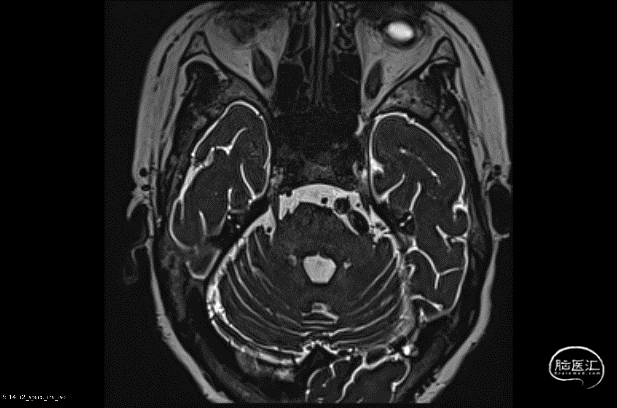

三叉神经痛微血管减压术:

患者信息:患者女,53岁,左侧面颊部发作性疼痛3年余,3年前无明显诱因出现左侧面颊部疼痛,突发突止,呈针扎样,无放射痛,咀嚼动作可诱发疼痛,疼痛科行神经根阻滞治疗症状有所缓解,1月前上述症状加重,考虑三叉神经痛,给予口服卡马西平药物治疗症状缓解。1周前症状再次加重,到院就诊,行三叉神经磁共振检测提示冗长的椎动脉压迫左侧三叉神经。

三叉神经痛微血管减压术:

患者信息:患者女,53岁,左侧面颊部发作性疼痛3年余,3年前无明显诱因出现左侧面颊部疼痛,突发突止,呈针扎样,无放射痛,咀嚼动作可诱发疼痛,疼痛科行神经根阻滞治疗症状有所缓解,1月前上述症状加重,考虑三叉神经痛,给予口服卡马西平药物治疗症状缓解。1周前症状再次加重,到院就诊,行三叉神经磁共振检测提示冗长的椎动脉压迫左侧三叉神经。